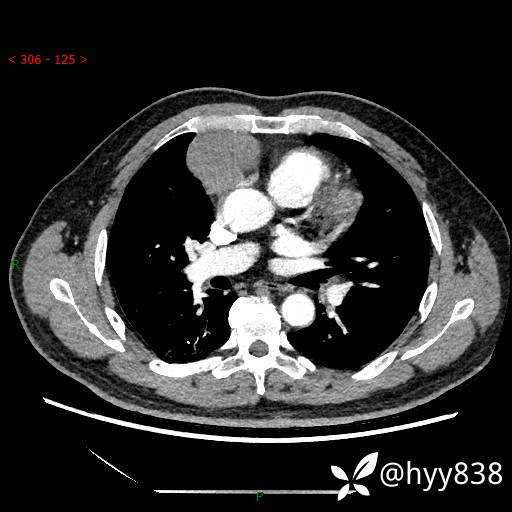

胸部CT平扫

动脉期+静脉期

各期CT值